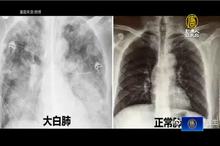

中共與天鬥清零失敗 陸網友轟「白肺心肌」

2023-01-03 16:38:54中共長達三年的清零封控失敗,現在疫情大爆發,出現「白肺」與「心肌炎」症狀的患者不斷蔓延至各個年齡層,有網友發文,家裡剛出生5天的新生兒,感染後遭醫院下病危通知書,右肺1/3出現白肺。由於中國本輪疫情中出現了大量「白肺」和「心肌炎」患者,中國網友更是創出了「白肺心肌」一詞,諷刺中共戰天鬥地的無效三年「清零」。目前,國際持續要求中共公布真實疫情數據,中國醫衛專家張文宏指出,過年期間,中國染疫比率可能高達80%,代表中國14億人口將有超過11億人染疫。